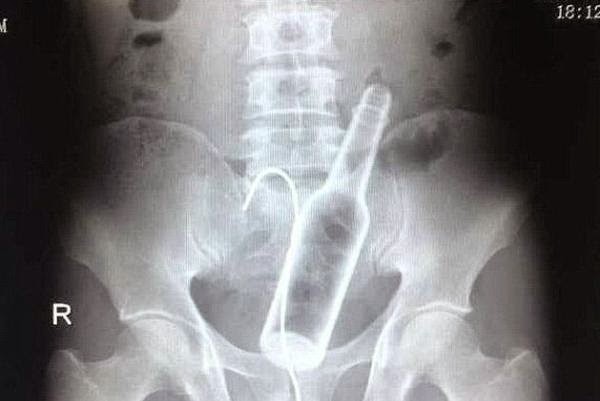

Una botella.